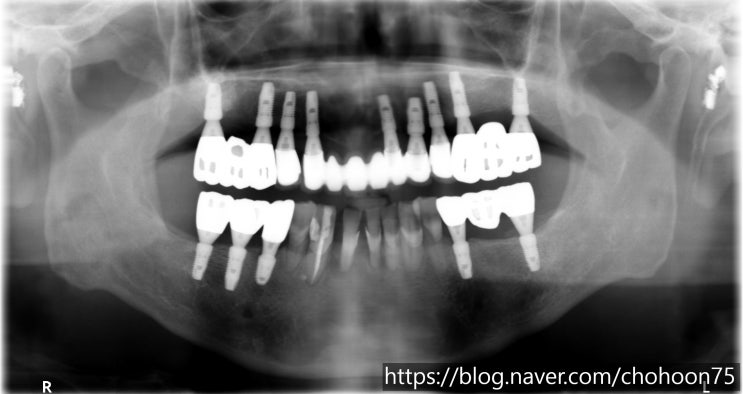

[조훈 치과] 치주 질환으로 인한 발치 후 임플란트 치료 증례

안녕하세요. 조훈 치과입니다. 치주 질환은 치아를 둘러싸고 있는 주변 조직에 생기는 염증성 질환으로 초...